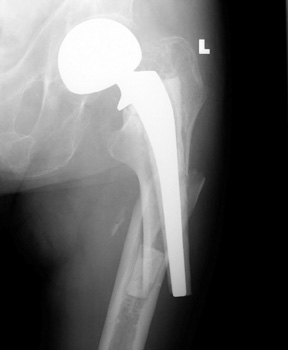

Most frequently occur near distal stem of femoral component

Osteopenia due to long periods of inactivity secondary to pain and disability predispose to insufficiency fractures after surgery when patients are ambulating more frequently.

FRACTURE—periprosthetic, in traction

Refracture of bone and of sideplate